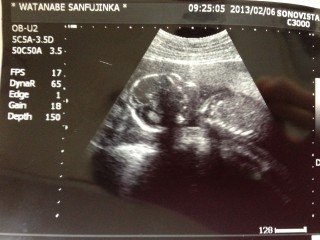

3回目の妊婦健診。 前回68g→今回251gと大きく成長していてびっくり! 若い女医さんだけど、エコー写真をまたもやもらえず…。 自分達で撮った動画からプリントアウトした写真なのでわかりづらいです…。 体外受精5回目でやっと授かった我が子なのでホントに愛おしくてたまりません。 逆子ちゃんらしいので何とかクルッと戻ってね(笑)